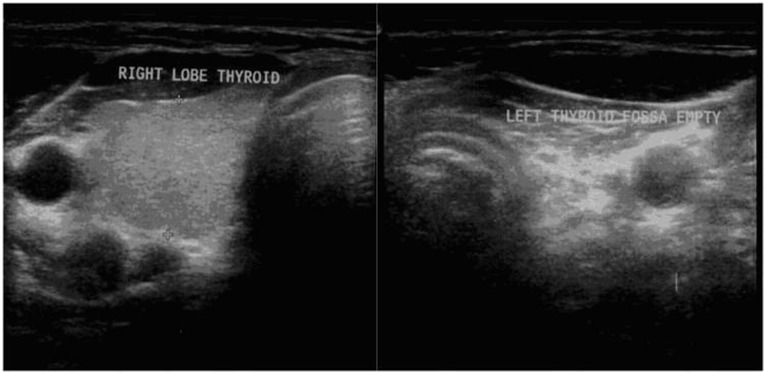

Thyroid hemiagenesis is a rare form of thyroid dysgenesis characterized by an absence of half of the thyroid gland. Developmental hemi-thyroid anomalies can result from either an abnormal descent or an agenesis of one lobe of the thyroid gland. We report a case of a 40-year-old woman with history of a longstanding gradually progressive thyroid swelling without any complication. An ultrasonographic examination diagnosed the absence of the left thyroid lobe and enlargement of the right lobe, which was confirmed on a computed tomography (CT) angiogram and a radionuclide scan of the neck. A cytological examination showed nodular goiter with cystic degeneration. Right subtotal thyroidectomy was performed and histopathological examination confirmed adenomatous goiter with degenerative changes. We report the rarity of the condition and emphasize the role of a comprehensive radiological, cytological, and radionuclide algorithm for an accurate preoperative diagnosis and subsequent management.